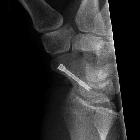

Röntgenbild

einer Kahnbeinfraktur eines 20jährigen Patienten. Operative Versorgung mit einer Boldschraube.